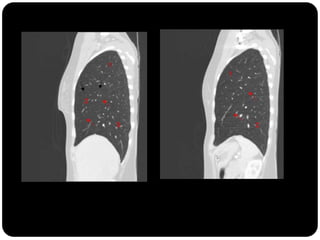

FISSURAS

Pulmões – lobos - fissuras

 Direito: 3 lobos (fissura oblíqua = maior e a horizontal =

menor)

 Esquerdo : 2 lobos (fissura oblíqua)

Vias aéreas

Traquéia       Fissuras interlobares: invaginações da pleura;

Brônquios

Bronquíolos

Alvéolos

Cisura maior esquerda mais

verticalizada

Pleura visceral